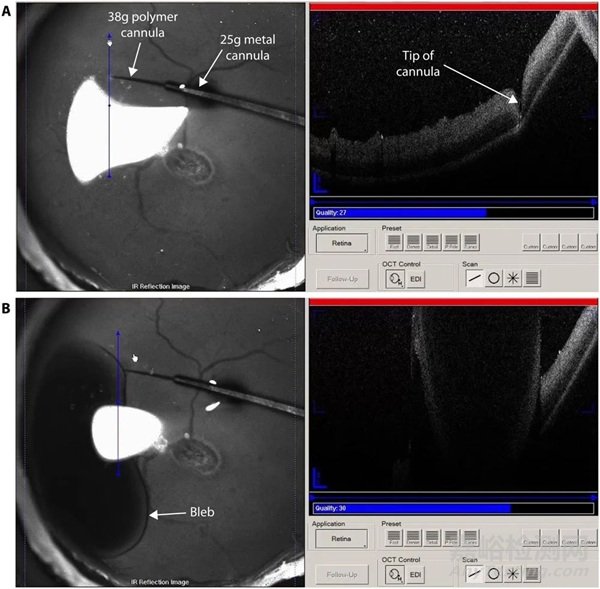

圖 4. 視網膜下注射過程中拍攝的紅外反射(左)和光學相干斷層掃描(OCT,右)圖像。(A)在即將啟動注射泵之前,套管完全壓入視網膜。(B)在紅外反射成像和光學相干斷層掃描成像下,可以看到液泡開始形成并擴張。光學相干斷層掃描的穿透深度不足以捕捉到完全形成的液泡的完整高度。由于鏡面反射偽像,光學相干斷層掃描圖像中液泡的輪廓看起來是上下顛倒的。請注意,紅外反射圖像中的亮區(qū)僅僅是反射光。